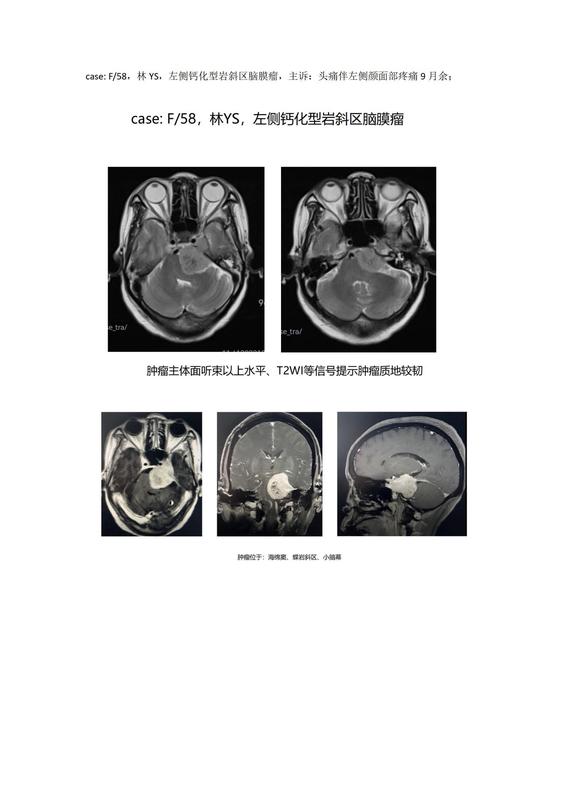

巖斜區(qū)腫瘤是所有神經(jīng)外科手術(shù)中最難的一類(lèi)手術(shù),而伴大塊鈣化的巖斜區(qū)腦膜瘤切除更是神經(jīng)外科手術(shù)中的“珠穆朗瑪峰”。向頂峰進(jìn)發(fā)。case:F/58,林YS,左側(cè)鈣化型巖斜區(qū)腦膜瘤,主訴:頭痛伴左側(cè)顏面部疼痛9月余;經(jīng)過(guò)長(zhǎng)達(dá)15個(gè)小時(shí)的手術(shù),順利全切腫瘤,患者術(shù)后疼痛癥狀消失,無(wú)神經(jīng)功能障礙,術(shù)后第九天痊愈出院。????????????????????